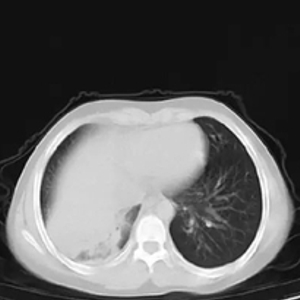

胸片上患儿的一侧肺部组织大面积变白

已经成了大叶性肺炎

男孩的影像学检查结果